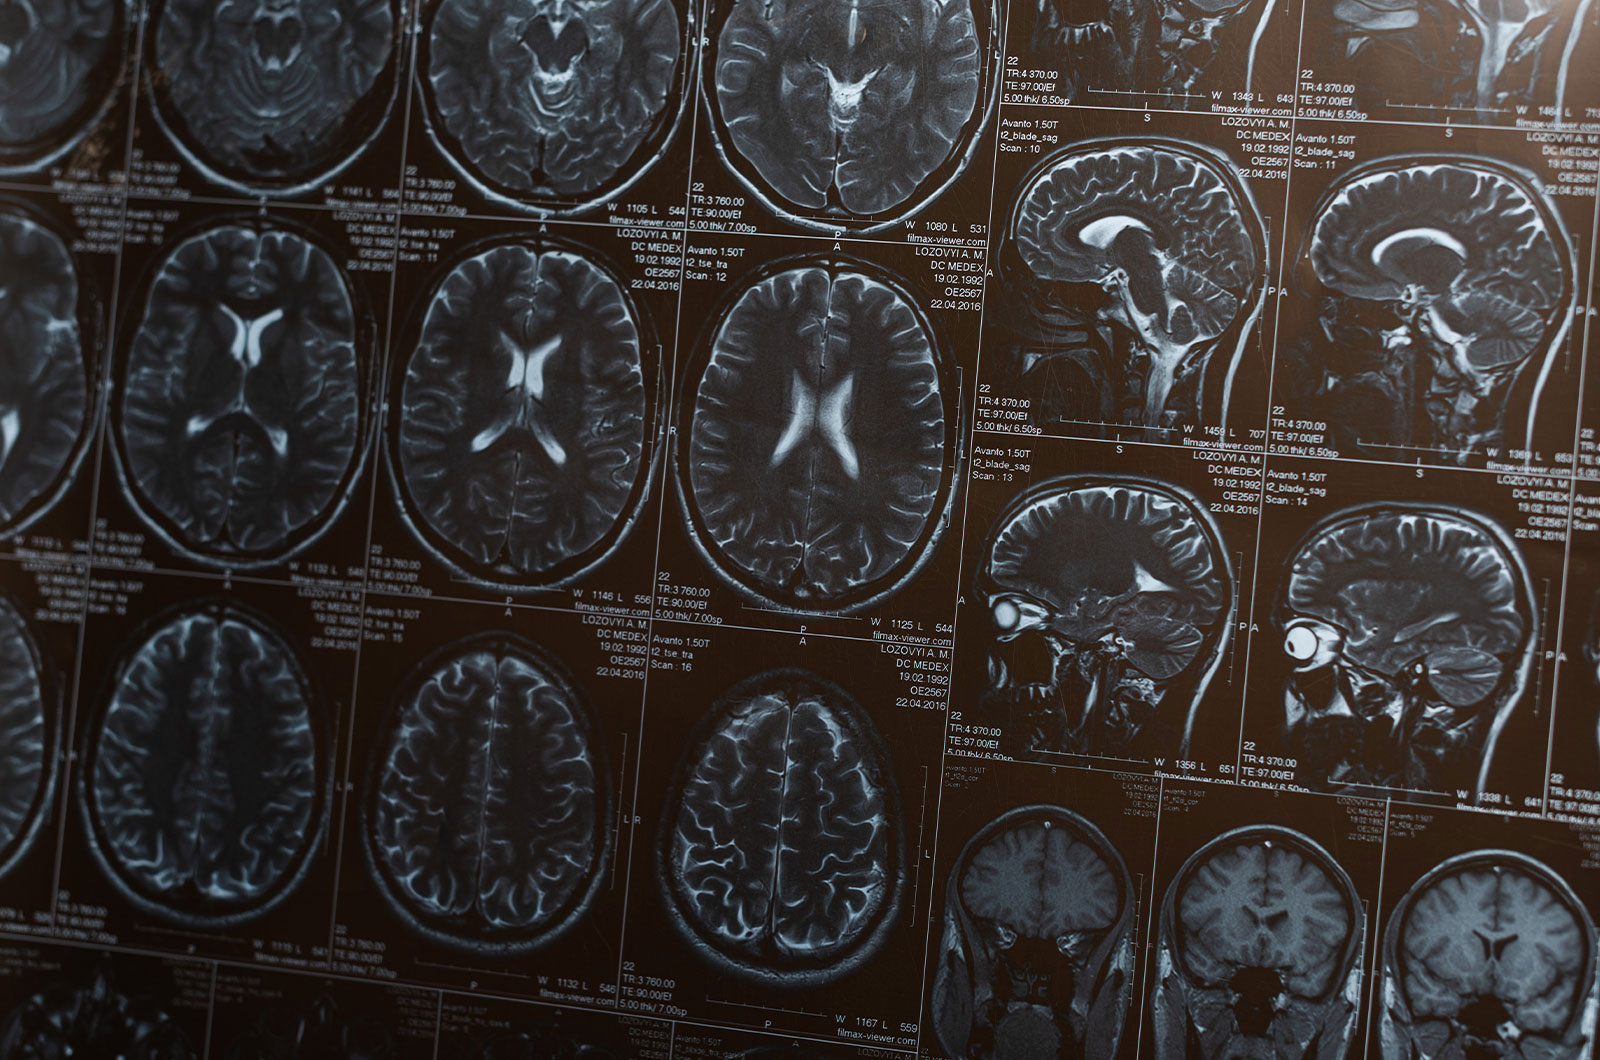

Schon bevor kognitive Störungen auftreten, lassen sich per Magnetresonanztomografie (MRT) im Gehirn Veränderungen an den Gefäßen beobachten. Vergleicht man die Gehirne von Gleichaltrigen mit und ohne Diabetes lassen sich Unterschiede feststellen, die als Brain age gap bezeichnet werden.

Um diesen Brain age gap zu messen, werteten schwedische Forscher die Gehirne von über 30.000 Probanden aus, bei denen im Durchschnitt von 64 Jahren ein MRT gemacht worden war. Bei rund 43 Prozent der Teilnehmer lag ein Prädiabetes vor, der Langzeitzuckerwert lag also zwischen 5,7 und 6,4 Prozent. Knapp 4 Prozent der Teilnehmer waren an Typ-2-Diabetes erkrankt (Langzeitzuckerwert ab 6,5 Prozent).